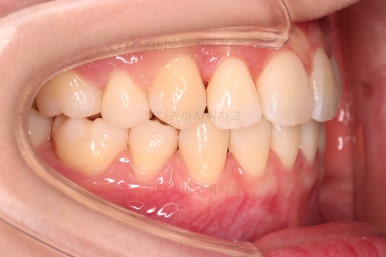

교합이 안정되었고, 치열도 가지런해졌으며 앞니 각도나 덧니 부분도 상당히 좋아졌어요.

부산교정전문의 전후 사진을 비교해 볼게요.

발치교정치고는 비교적 짧은 기간인 20개월만에 치열, 교합, 뻗친 느낌, 원하는 만큼의 입매 등 많은 점이 잘 개선된 치료였습니다.